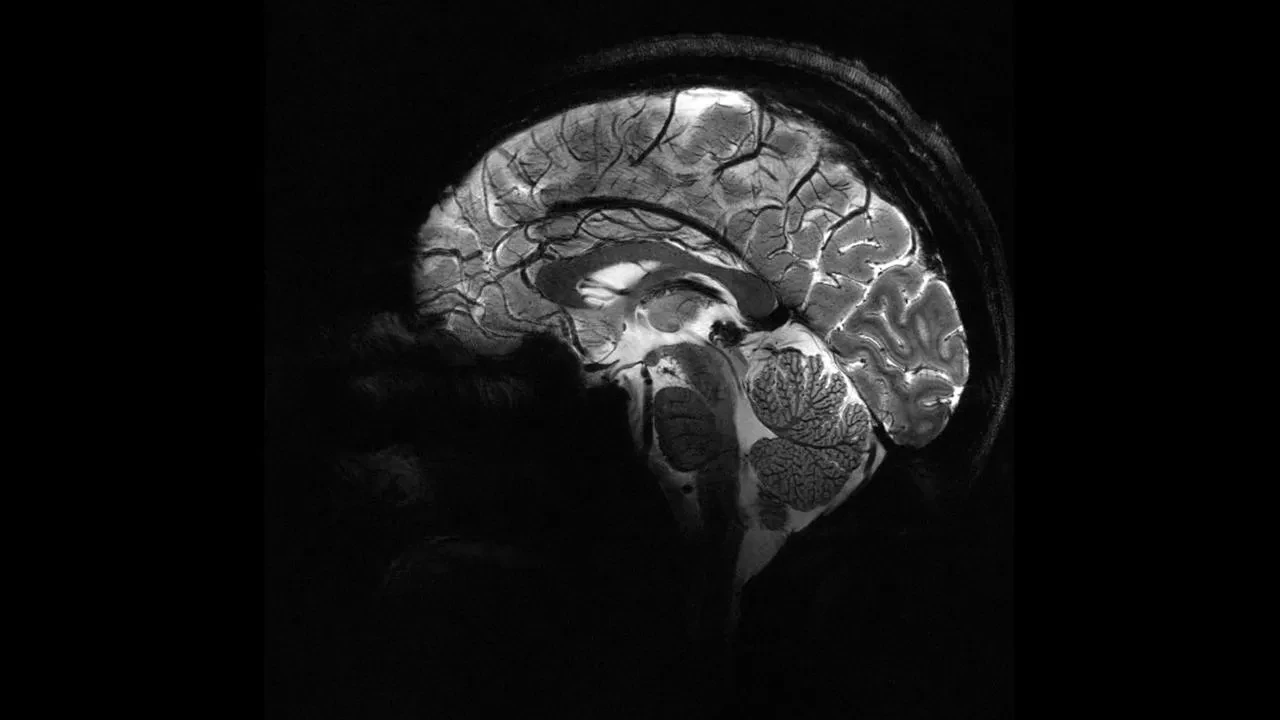

Epilepsiye farklı nedenler yol açsa da, vakaların yaklaşık yüzde 30’u beyindeki yapısal anormalliklerden kaynaklanıyor. Ancak bu lezyonlar, özellikle de beynin kıvrımlarının derinliklerinde saklı olan en küçük olanlar, çoğu zaman MR görüntülerinde fark edilmiyor.

Melbourne Kraliyet Çocuk Hastanesi’nden pediatrik nörolog Emma Macdonald-Laurs liderliğindeki ekip, çocuk beyin görüntüleri üzerinde yapay zekâ modeli eğiterek yaban mersini büyüklüğünde ya da daha küçük lezyonları ortaya çıkarmayı başardı.